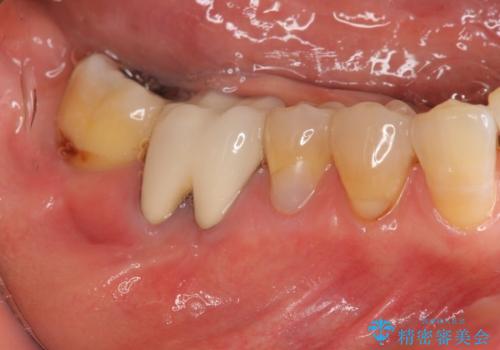

- 右下奥歯からの排膿、痛みの改善を希望され来院されました。

薄い歯質の歯牙に過大な負荷がかかり亀裂を生じ大臼歯分岐部に大きな骨吸収を認め、抜歯を余儀なくされる状態です。

抜歯を行ったのち前後の歯に軽度の動揺があるため、インプラントではなくブリッジによる補綴処置を行い機能回復を行いますが、近心傾斜した第2大臼歯をマイクロインプラントを用いた小矯正を行うことで歯軸方向を改善し、神経を温存した状態でブリッジ製作できるよう前処置を行います。